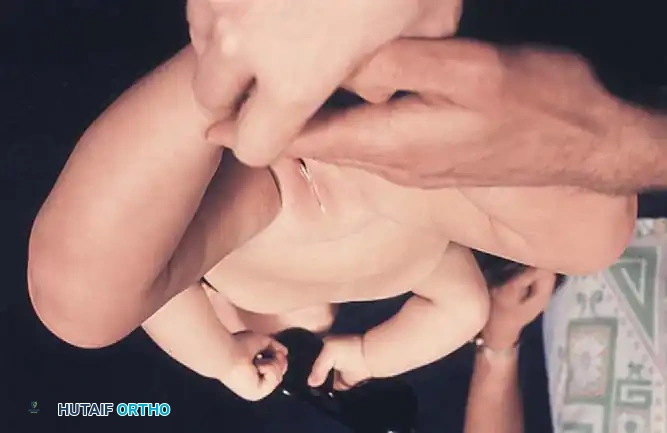

Routine clinical screening must include the Ortolani test and the provocative maneuver of Barlow.

* Ortolani Maneuver: Performed by gently abducting and elevating the flexed hip to detect the reduction of a dislocated femoral head into the true acetabulum. A palpable "clunk" indicates a positive test.

* Barlow Maneuver: Detects potential subluxation or posterior dislocation by applying direct posterior pressure on the longitudinal axis of the femur while the hip is in adduction.

Fig 27-1: Ortolani maneuver for routine screening. The examiner stabilizes the pelvis, places the index and middle fingers over the greater trochanter, and gently abducts the hip.

Surgical Warning: Both tests require a relaxed, pacified child. Forceful maneuvers must be strictly avoided, as they can damage the delicate infantile articular cartilage or cause iatrogenic instability.